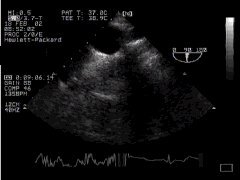

Returning the probe to the short axis view (0o) and widthdrawing it slowly, we eventually cut the aortic arch. It's easy to see that despite the plane of the probe being 0o, we will visualise the arch as an oblong structure - we are effectively visualising the "long axis" of the arch - 'Aortic Arch LAX'. Note that as we move more proximally, the trachea becomes interposed, and we lose the arch and vessels coming off it.

Arch aorta - transverse section CLICK FOR VIDEO: Arch aorta lax view